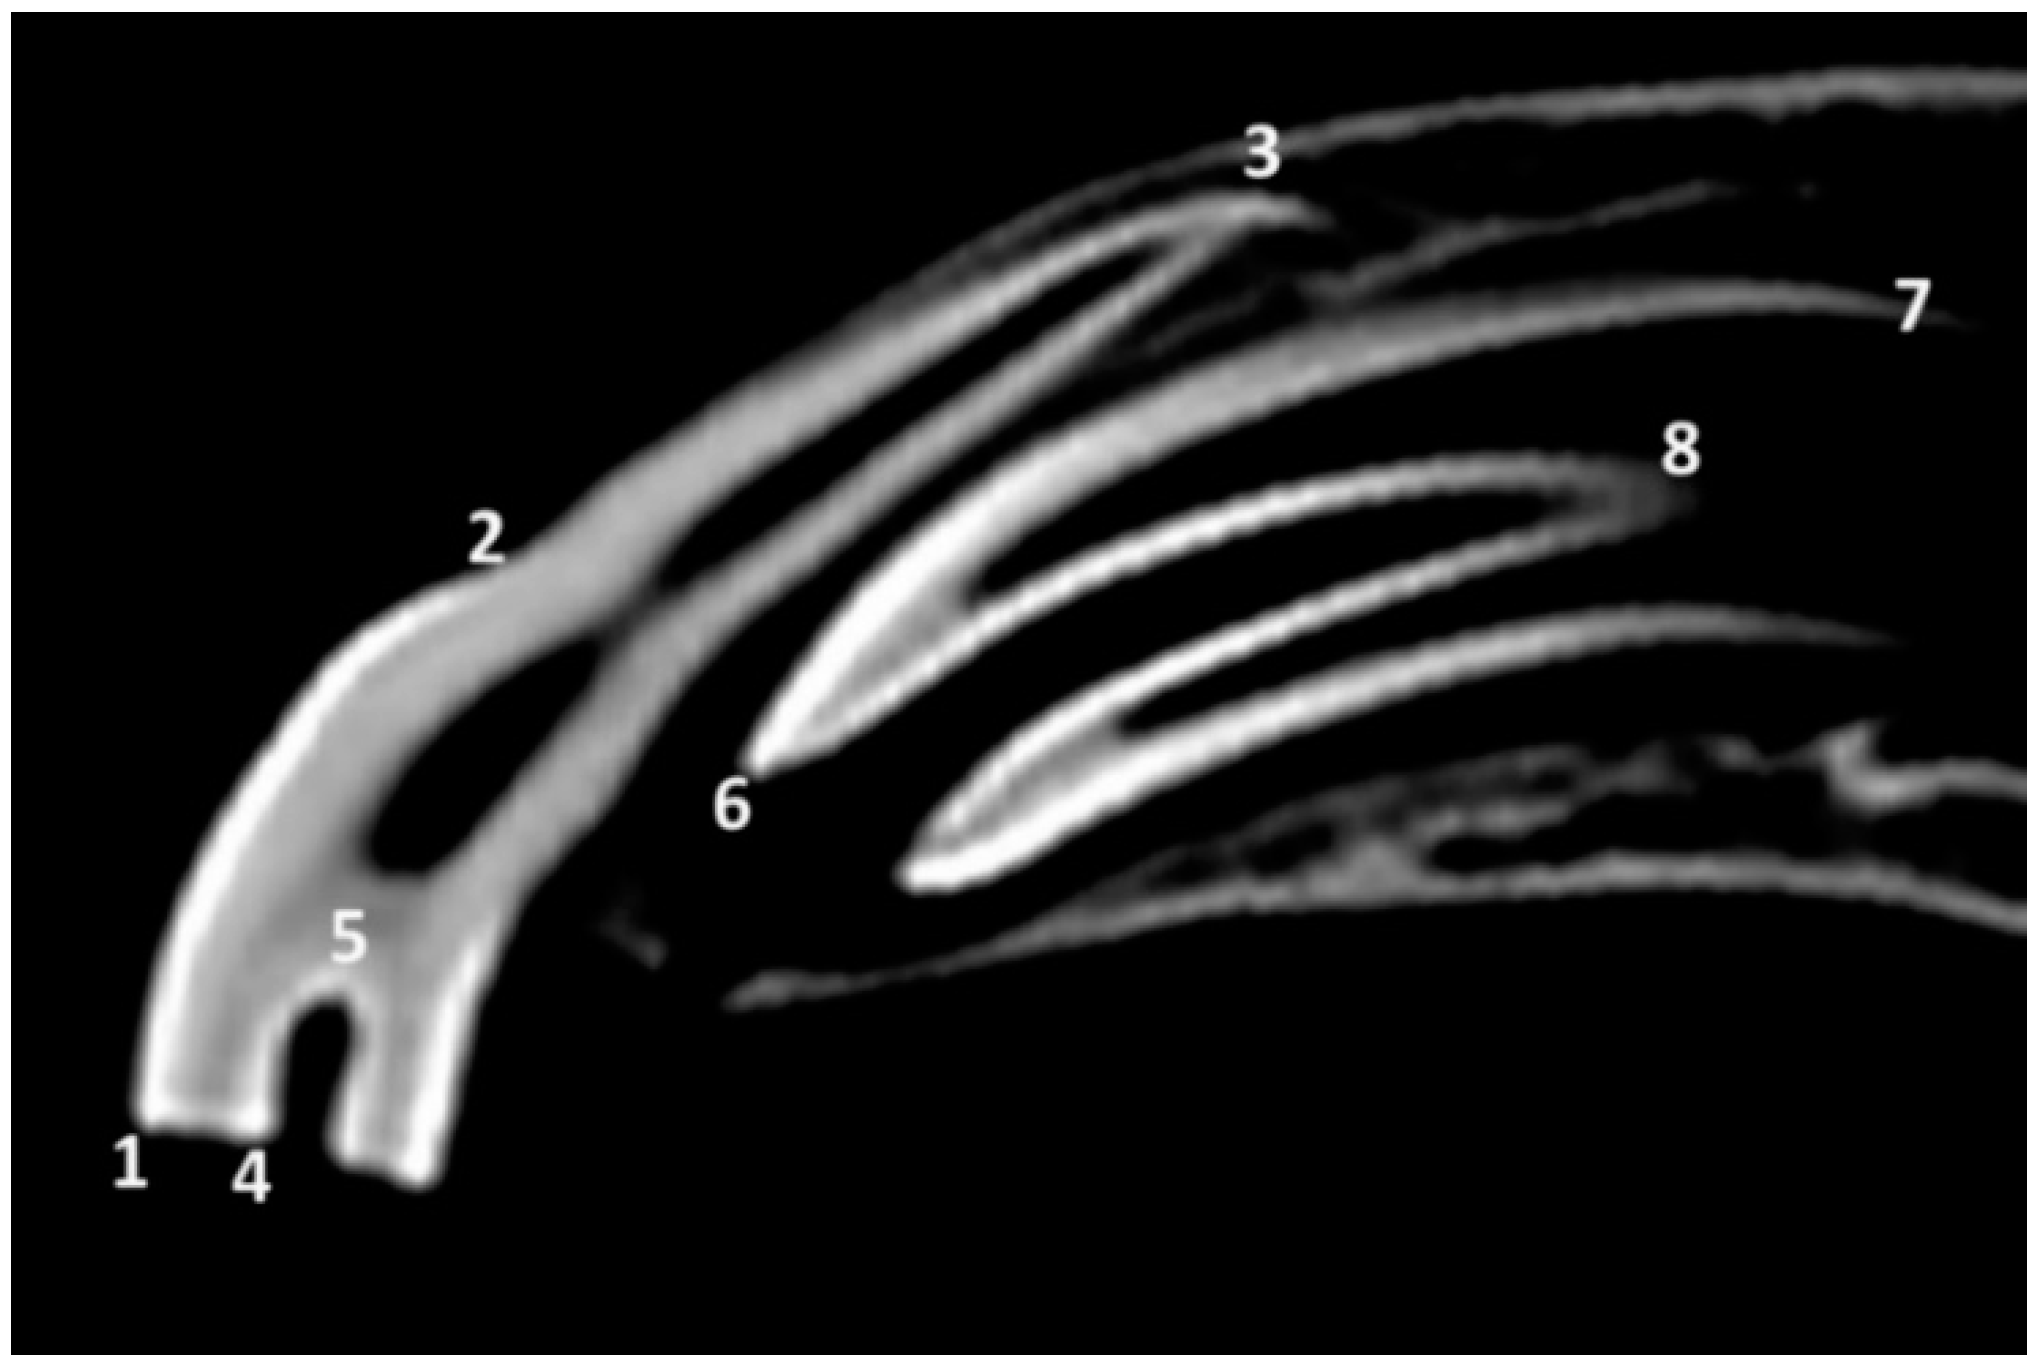

3.2. Radiographic and CT Studies

4.1. Deciduous Incisors: Radiographic and CT Studies

4.2. Permanent Incisors and Alveoli: Radiographic and CT Studies